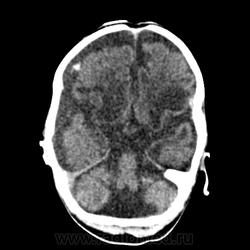

Уважаемые, Коллеги! Ребенок почти 2 месяцев, с основными симптомами на томограммах вроде бы все понятно, но остался один, не ясный для меня, момент! Подскажите, пожалуйста, что за гиперденсивное включение в субарахноидальном пространстве правой лобной области.

При врожденных патологиях чего только не увидишь. Вопрос: а как оно влияет на Ваше заключение и лечение? Это принципиально? Кальциноз в арахноидальных оболочках редкость у детей до 6-10лет, тут Вы правы. А вот потом - не редкость. При инфекционных менингитах как последствие - вполне. Вы указали -инфекция. Какая?

Возможно на лечение и дальнейшую тактику ведения ребеночка описание этого "включения" никак не повлияет, у него есть проблемы в головном мозге куда более серьезней! Интерес для себя. Что касается инфекции, то в анамнезе ВУИ, какая именно не указано. Смутило то, что плотность этого "включения" максимум до 90 HU (для кальцината маловато). И судя по томограммам в костном режиме имела место интранатальная травма.

Мне кажется все же это кальцинаты. Измерения иногда врут, особенно если мерять мелкие объекты.

Я тоже думаю, что это кальцинат, плотность нормальная для кальцината у новорожденного. Мультикистозная энцефаломаляция часто является исходом герпетического менингоэнцефалита.